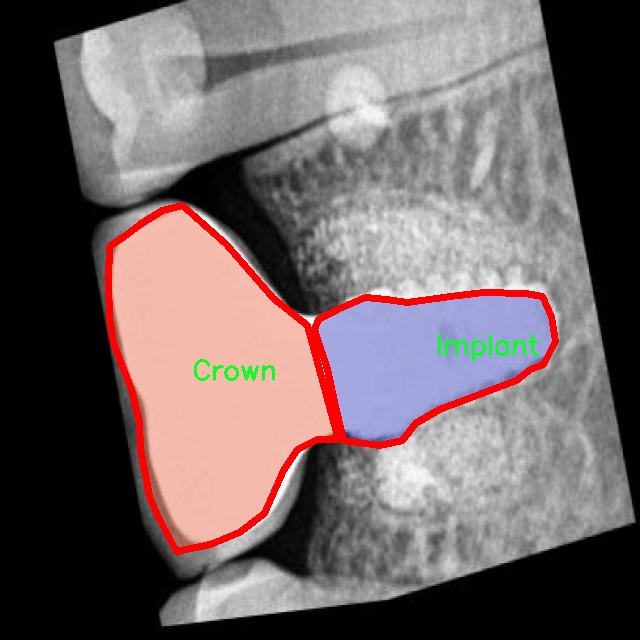

图片效果

在本研究中,我们采用了名为“rvg-v1”的数据集,以支持对牙片牙齿病变图像分割系统的训练,旨在改进YOLOv8-seg模型的性能。该数据集专门为牙科影像分析而设计,涵盖了多种常见的牙齿病变类型,具有重要的临床应用价值。数据集的类别数量为18,涵盖了从常见的牙齿病变到复杂的牙科情况,提供了丰富的样本以供深度学习模型进行训练和验证。

“rvg-v1”数据集中的类别包括:脓肿(Abscess)、磨损(Attrition)、骨丧失(Bone loss)、牙石(Calculus)、龋齿(Caries)、牙冠(Crown)、囊肿(Cyst)、填充物(Filling)、骨折线(Fracture line)、分叉(Furcation)、阻生牙(Impacted)、植体(Implant)、神经(Nerve)、根管治疗(Root canal treated)、根片(Root piece)、窦道(Sinus)、未萌出牙(Unerupted)以及一个通用类别(object)。这些类别不仅涵盖了牙齿常见的病变,还包括了一些较为复杂的牙科情况,能够帮助模型更全面地理解和识别牙科影像中的不同病变特征。